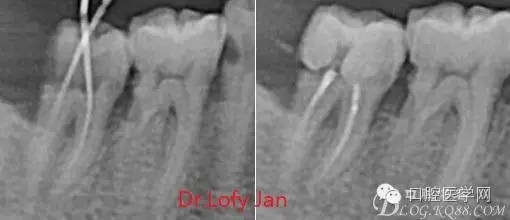

前言:自己做的一些曲面斷層片在未試尖根管治療中的病例整理,發(fā)現(xiàn)問題很多包括自身的,技術(shù)的,還有設(shè)備的問題,予以總結(jié)整理并期待進(jìn)一步提高。

根管治療術(shù)是牙體牙髓疾病治療中最復(fù)雜和最關(guān)鍵的治療項目。根管充填材料抵達(dá)根尖、并能嚴(yán)密堵塞根尖孔,是確保根管治療效果的關(guān)鍵指標(biāo)。為了保證根管充填到位,醫(yī)生需要在術(shù)前照牙片以了解牙根根管的數(shù)量、彎曲程度和長度,在術(shù)中有時需要插針照牙片來精確測量根管長度,術(shù)后必須照牙片以確定是否根管充填到位,如果欠填或超填,就需要重新充填、重新照牙片確認(rèn),直到根管充填到位。所以,在患者接受根管治療時有時會反復(fù)照牙片。

病例分析:曲面斷層片在x線輔助診斷與檢查中目前大多數(shù)文獻(xiàn)和著作都建議只能作為初診拍片檢查手段,不能作為終末疾病的確診與手術(shù)療效的評價指標(biāo),臨床大部分中小型門診都因為設(shè)備不齊全導(dǎo)致信息偏差很大。